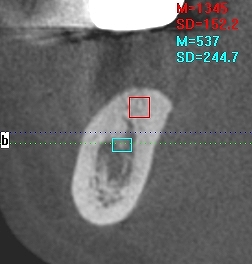

インプラントが成功するかは診査診断、埋入時のCTデータがすべてかと思います。埋入後にも確認を取ります。